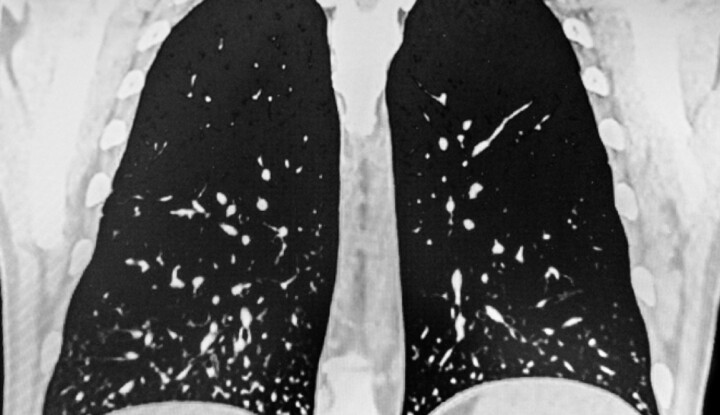

A hisztoplazmózis

A hisztoplazmózis egy gombafertőzés kapcsán kialakult kórkép, melyet a Histoplasma capsulatum nevű kórokozó okoz.